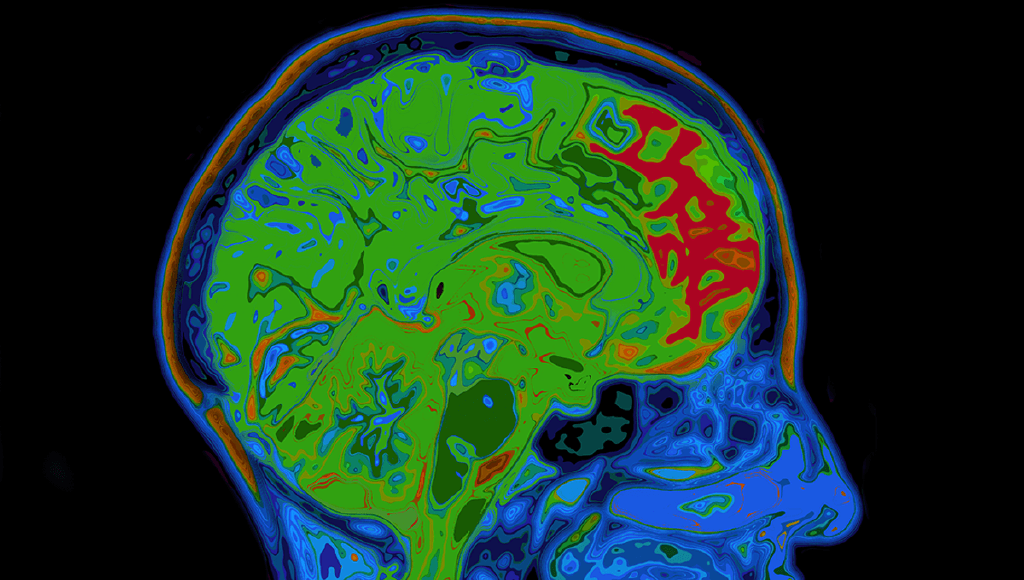

Rare Syndrome Leaves Man Living In "Groundhog Day"

“Every day is a repeat of the day before."